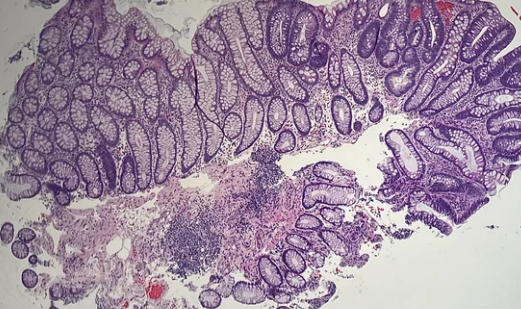

관상 선종은 대장 점막의 선세포가 비정상적으로 증식해 생기는 선종성 용종입니다.

- 용종(폴립) → 장 점막이 혹처럼 튀어나온 모든 병변

- 선종 → 그중에서 암으로 발전 가능성이 있는 조직

👉 모든 용종이 선종은 아닙니다.관상 선종은 선종 중에서도 가장 흔하고 비교적 위험도가 낮은 유형입니다.

종류 특징 암 위험도 관상 선종 가장 흔함 낮음~중간 융모 선종 표면이 융모 형태 높음 관융모 선종 혼합형 중간~높음 크기와 조직 형태가 암 진행 위험도를 결정합니다.